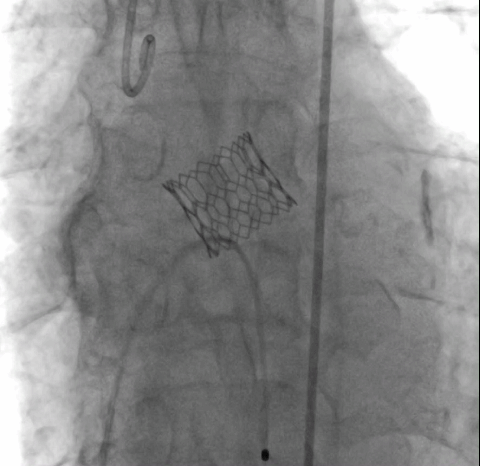

经术前详尽影像学重建、评估及病例讨论,最终决定在脑氧监测下对患者实施经左侧颈总动脉TAVI手术。术中左侧颈总动脉多次预扩后顺利置入血管鞘至升主动脉,跨瓣成功后先以23#球囊预扩,再“0位”植入25# Renatus介入主动脉瓣。手术耗时约2小时,介入主动脉瓣植入位置理想,功能表现良好,主动脉瓣峰值流速及平均跨瓣压差分别降至1.75m/s和5mmHg,造影及TEE观察仅有轻微瓣周漏,无中央型反流。术后左颈总动脉造影无明显狭窄,手术全程脑氧饱和度正常,无传导阻滞、无冠脉异常。

瓣膜“0位”释放 术后主动脉根部造影